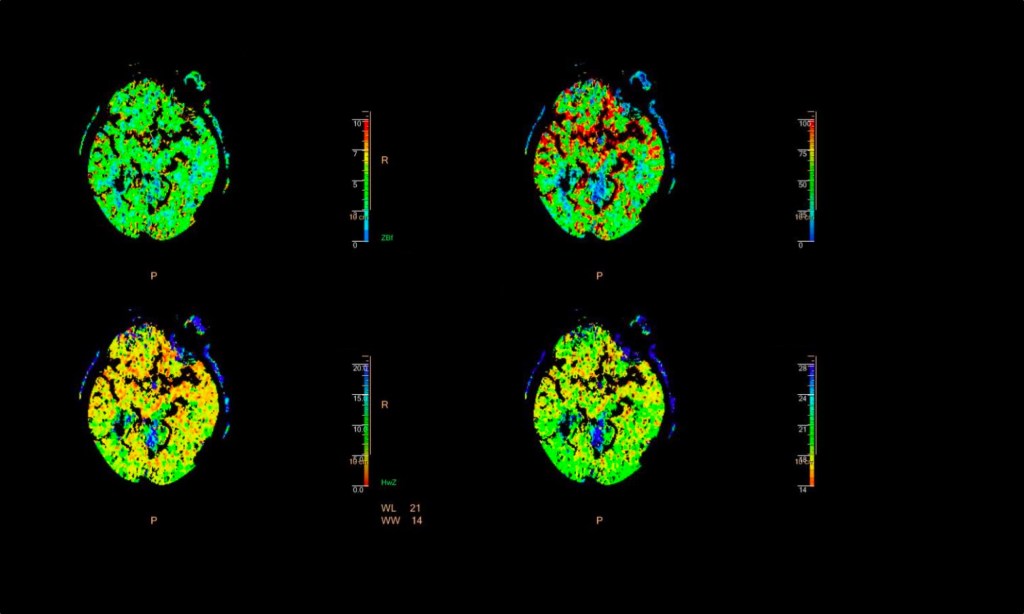

Teil 3 der kleinen Reihe mit schönen, nach meinem Beurteilungsvermögen gut gemachten, Papern zum Thema COIVD-19. Teil 1, in dem es um die Schutzwirkung der Impfung vor COVID-Folgeerkrankungen geht, findet ihr hier, Teil 2 (neuropsychiatrische Folgeerkrankungen von schweren COVID-Verläufen) hier. Nukular, das Wort heißt nukular Heute soll es um nuklearmedizinische Bildgebung gehen. Hier haben ja…

-